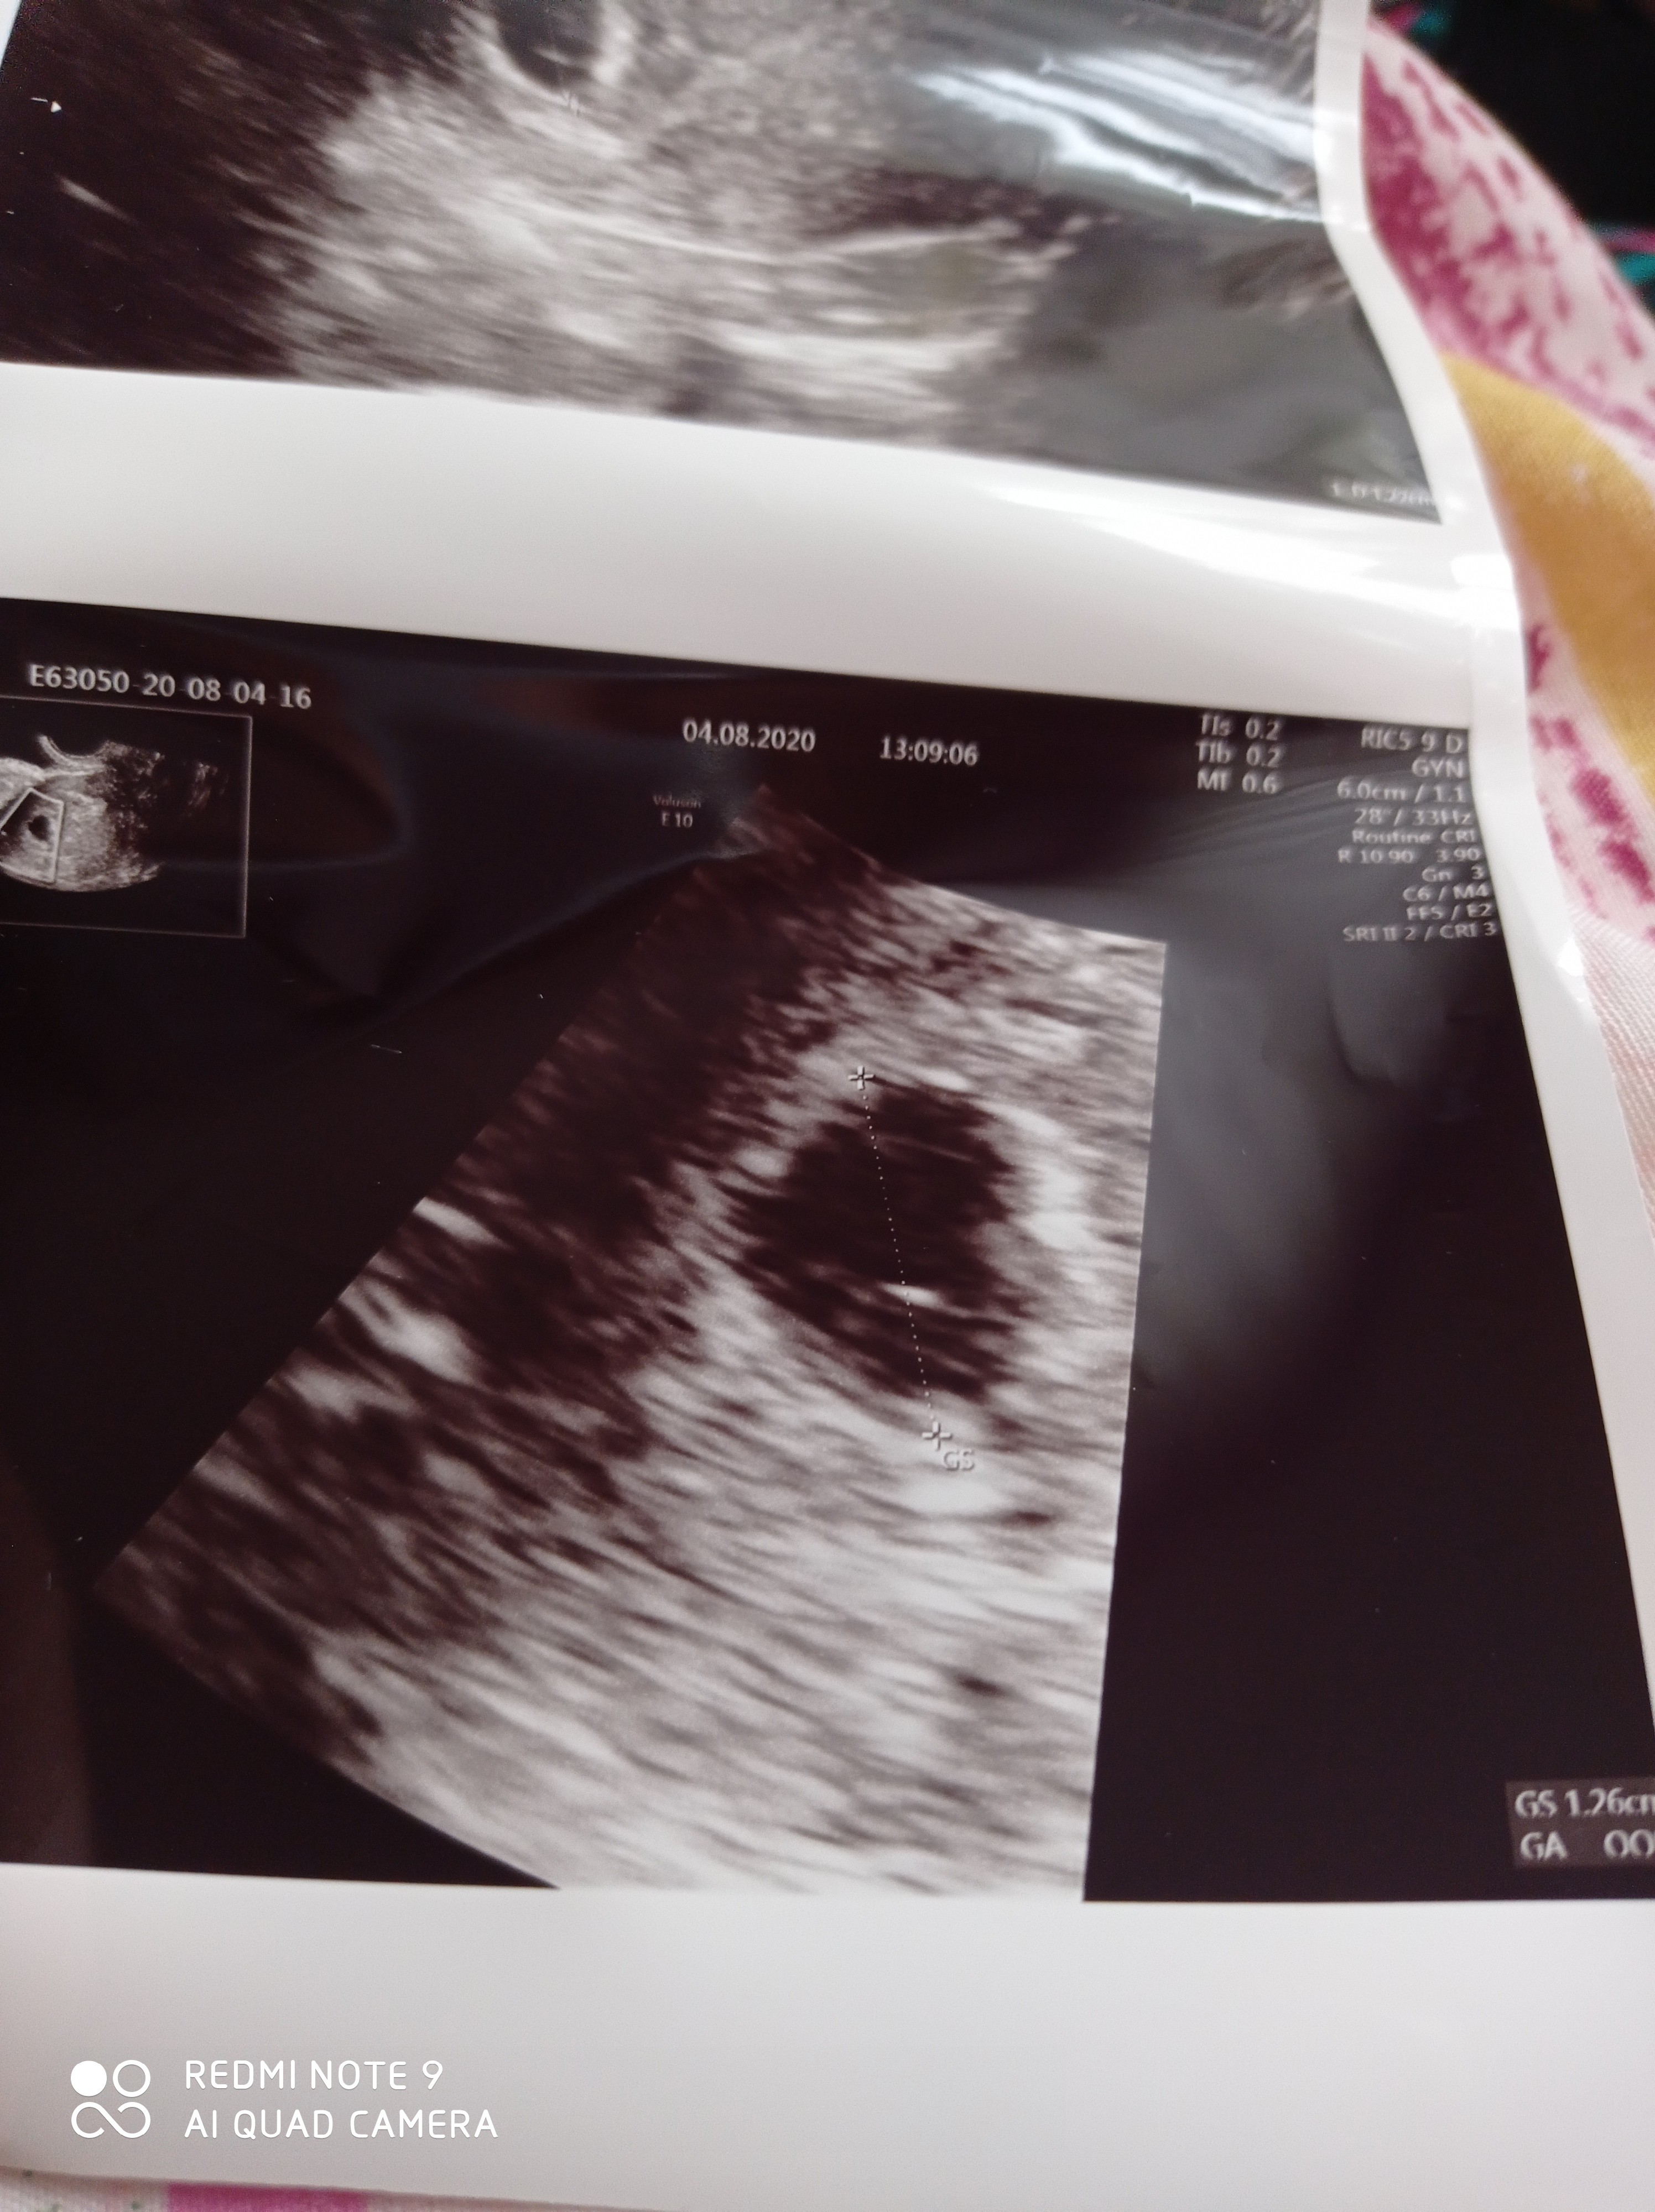

Wyszlam od lekarza i jestem spokojniejsza i szczesliwa ❤️❤️

Z usg 7w6d z OM 7w5d 💙❤️ mój mały ideał 😁

Tętno 174, doktor powiedział że idealne 😜

Pierwsze foto ktosia 😂

Załączniki

• IMG_20200804_170423.jpg

IMG_20200804_170423.jpg

1,2 MB · Wyświetleń: 120